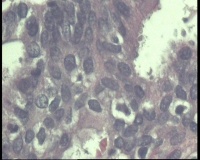

镜下见子宫内膜腺体异型增生,呈乳头状,筛网状排列,细胞核圆形,大小尚均匀,可见少量核分裂像,部分区域鳞化,间质少,部分区域无间质,间质有坏死

有些区域不能除外浆液性癌,最好做一做免疫组化协助鉴别。

浆液性癌!建议P53;P16'ER;PR等确认!